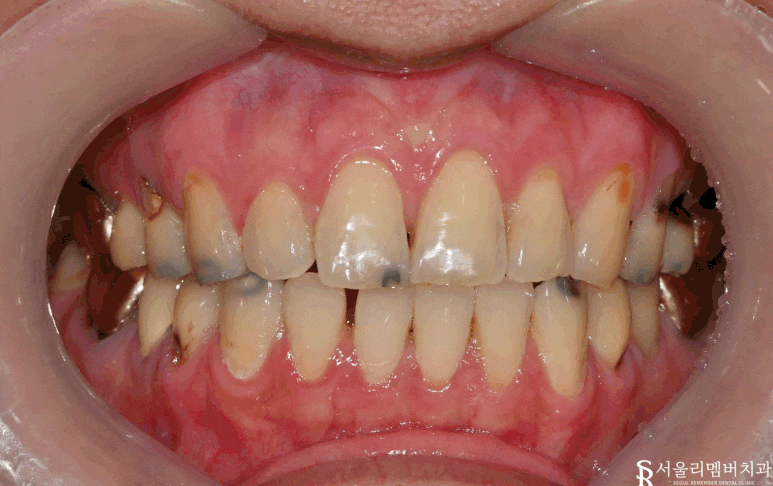

구내사진

곳곳에 심한 충치들을 확인할 수 있습니다.

이전과 비교해 보면

앞니 충치들을 모두 제거하고 깔끔하게

심미 레진 치료된 것이 보입니다.